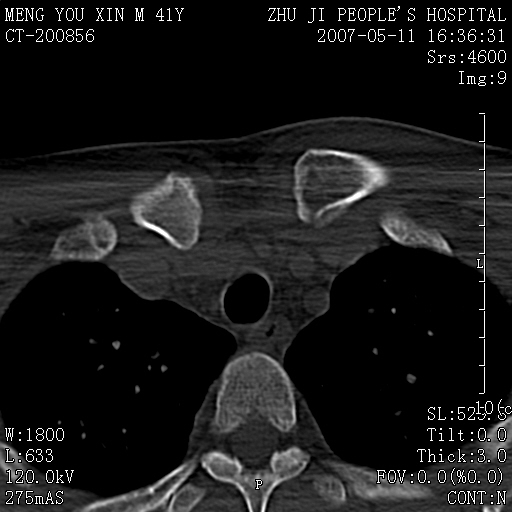

标题: CT8190:左锁骨胸骨端骨病,请会诊.

一周前左肩部酸痛,三天前颈部扭伤,后颈部摄片示颈椎病.现胸锁关节处肿痛明显.无发热.自诉三年前车祸安全气囊弹出.

左侧锁骨近端膨大,骨皮质中断,并见少许骨膜反应,内见破坏,边缘见筛孔征,无硬化.因此考虑骨巨细胞瘤可能.

双侧胸锁关节未见明显异常改变。

1,不支持结核,此例胸壁肿胀不明显,锁骨后方是局限性肿物而非脓肿,考虑为恶性肿瘤2,左侧锁骨近端膨大,骨皮质中断,并见少许骨膜反应,内见破坏,边缘见筛孔征,无硬化.因此考虑骨巨细胞瘤可能.